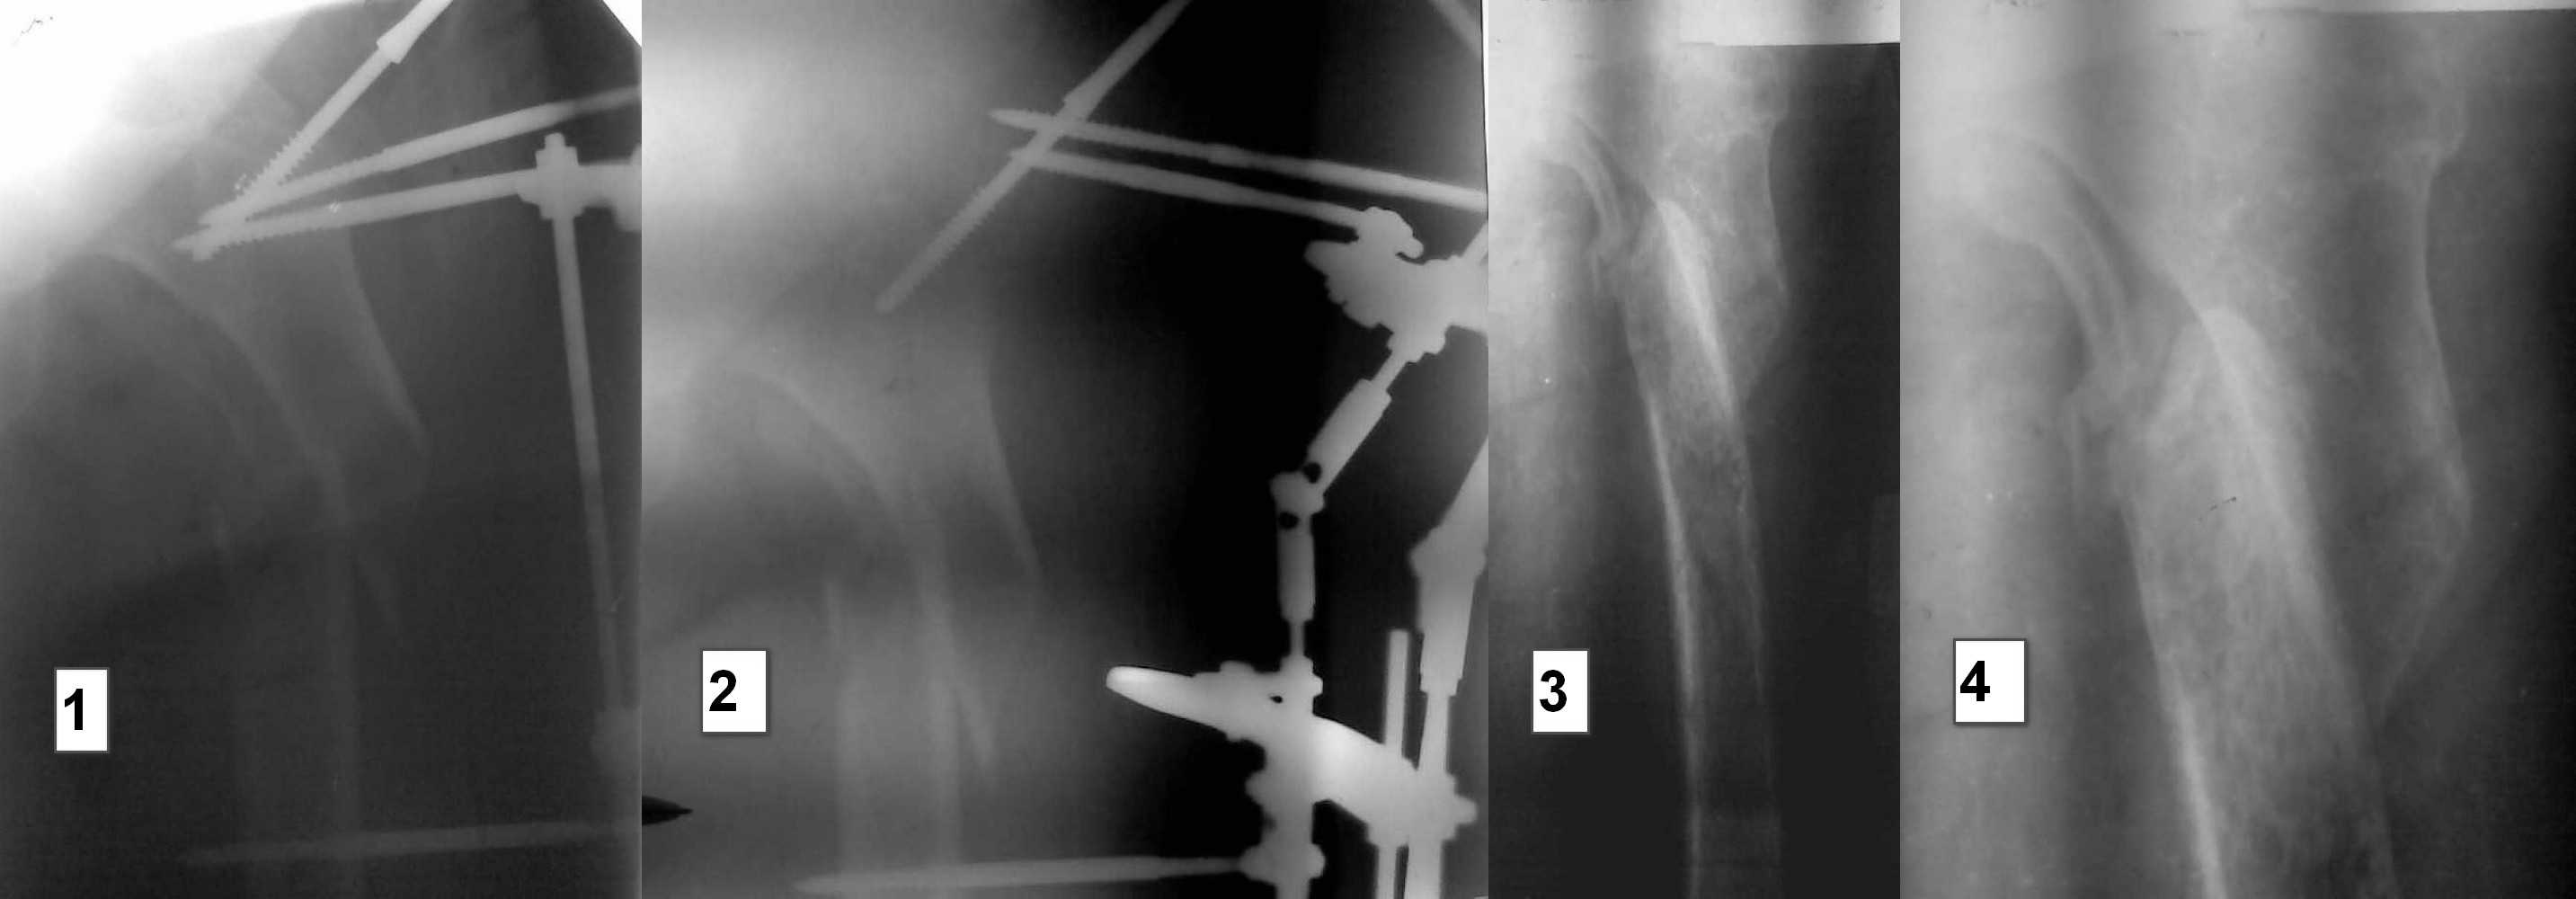

Фистула функционирует от случая к случаю - последние 2 дня выделений небыло, сделали контрастирование (с трудом вошло 5 мл контраста). Признаков воспаления в зоне поражения нет, лабораторные показатели в пределах нормы. Судя по распростарнению контраста - локальный остеомиелит в месте расположения стержня АВФ

План следующий: 1.контрастирование зелёнкой, ФНСЭ, дренирование+бусы с антибиотиком

2. если нет распространеия контраста в область грушевидной ямки и места перелома - БИОС стержнем с цементным покрытием

3. если распространение в указаные области есть - дренирование, бусы, заживелние раны, дистракция отломков, БИОС

Dr Alex, добрый день. Я за двухэтапное лечение, если есть проблемы с АВФ(нежелание больной или докторов)как вариант наложить ДСВ, 2 спицы через бугристость ББК, груз 10% от массы больной, иссечь гнойный очаг и подержать до заживления.Рентген-контроль на ДСВ, если удалось растянуть по длине, то идти на закрытый синтез. Не могу разглядеть на снимках "ушел" малый вертел или нет? Если перелом из чрез-под-вертельных, то надо брать длинный гамма-гвоздь. Без ЭОПа, будет .опа, но очень интересно, 2 рентген-аппарата, лаборант бегает матерится, шейка спицами маркируется, ах молодость-молодость, приятно вспомнить.

В субботу проведна спица за бугристость ББК, вес 10 кг. Сегодня контрольные снимки - видимого удлинения в соотношении фрагментов нет, патологическая подвижность осталась. Больная тяжело переносит вынужденное положение, беспокоит боль в области перелома. Свищ с воскресенья не функционирует, признаков воспаления в проксимальном отделе бедра нет, лабораторные показатели в норме.

Малый вертел с небольшим фрагментом кортикала отломан.